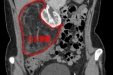

【医疗动态】花季少女得肿瘤 微创手术建奇功